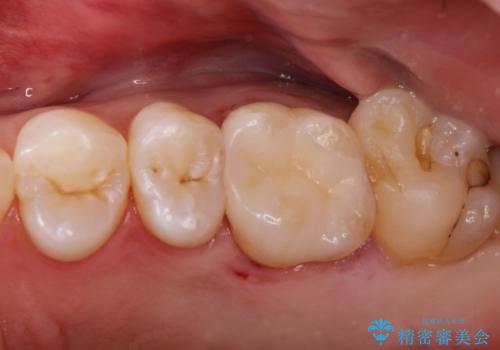

メタルフリー セラミックインレー

- メタルフリーの治療を希望されて来院されました。

セラミックインレーの治療を2回の来院で終了しております

e-max プレスインレーにて修復治療を行っているため適合性及び審美性の高い治療を行うことができます